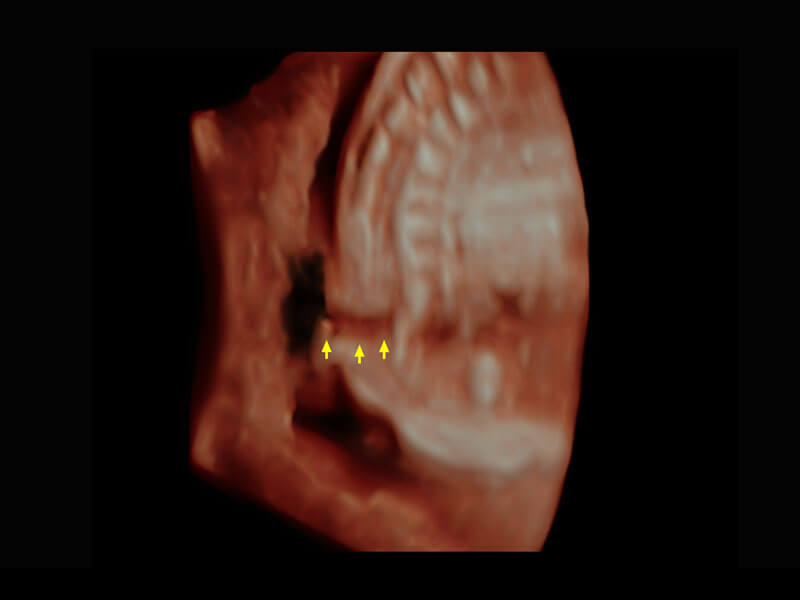

P60搭载一系列胎儿心脏成像技术,实现精细的胎儿心脏评估。

右室双出口

胎心容积成像